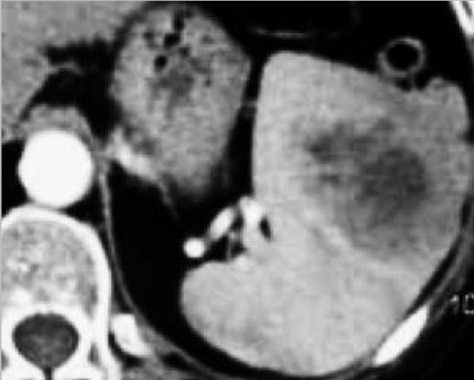

Image radiologique TDM en coupe axial

d'une autre lymphome Hodgkinien maligne de la rate

avec aspect lesionel des nodules ovalaires

hypodensite en rapport de parenchyme de la rate .

Lesions sont en s'observer facile au phase de veine

porte |